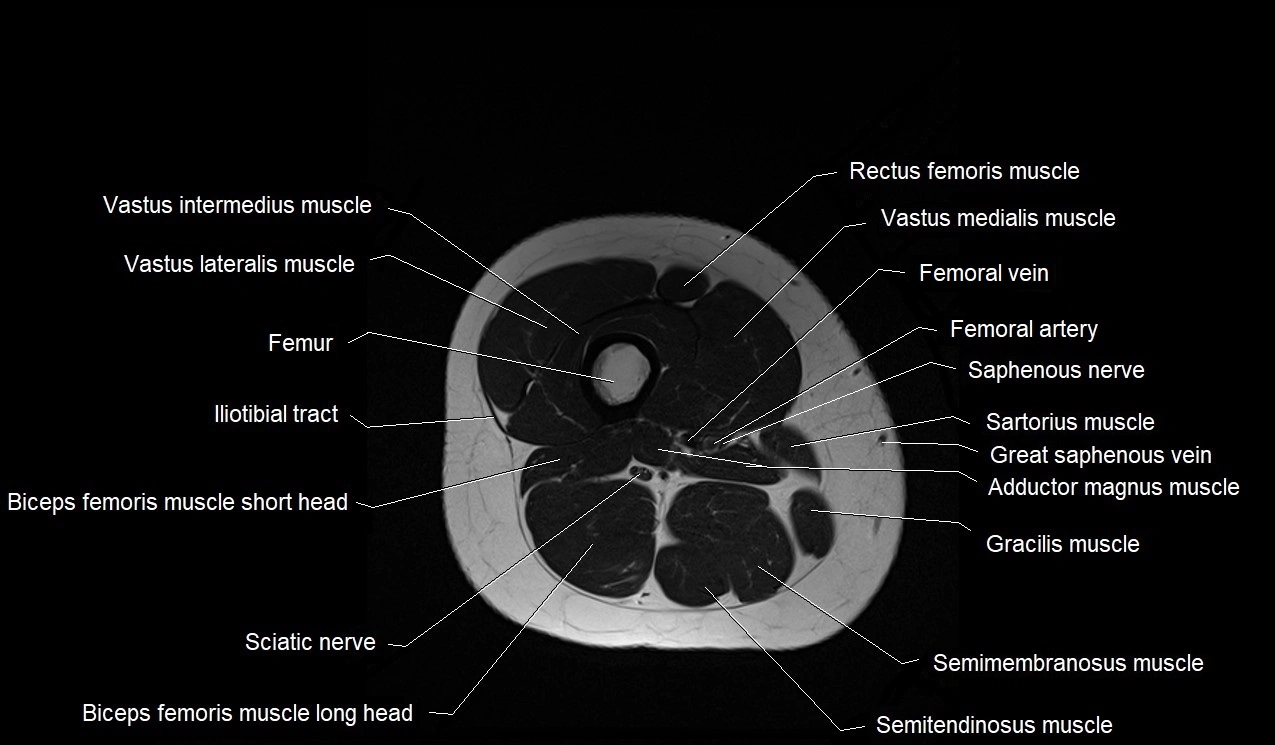

- Biceps femoris muscle (Long head)

- Biceps femoris muscle (Short head)

- Common fibular nerve

- Femur

- Gracilis muscle

- Iliotibial tract

- Rectus femoris muscle

- Sartorius muscle

- Semimembranosus muscle

- Semitendinosus muscle

- Vastus intermedius muscle

- Vastus lateralis muscle

- Vastus medialis muscle